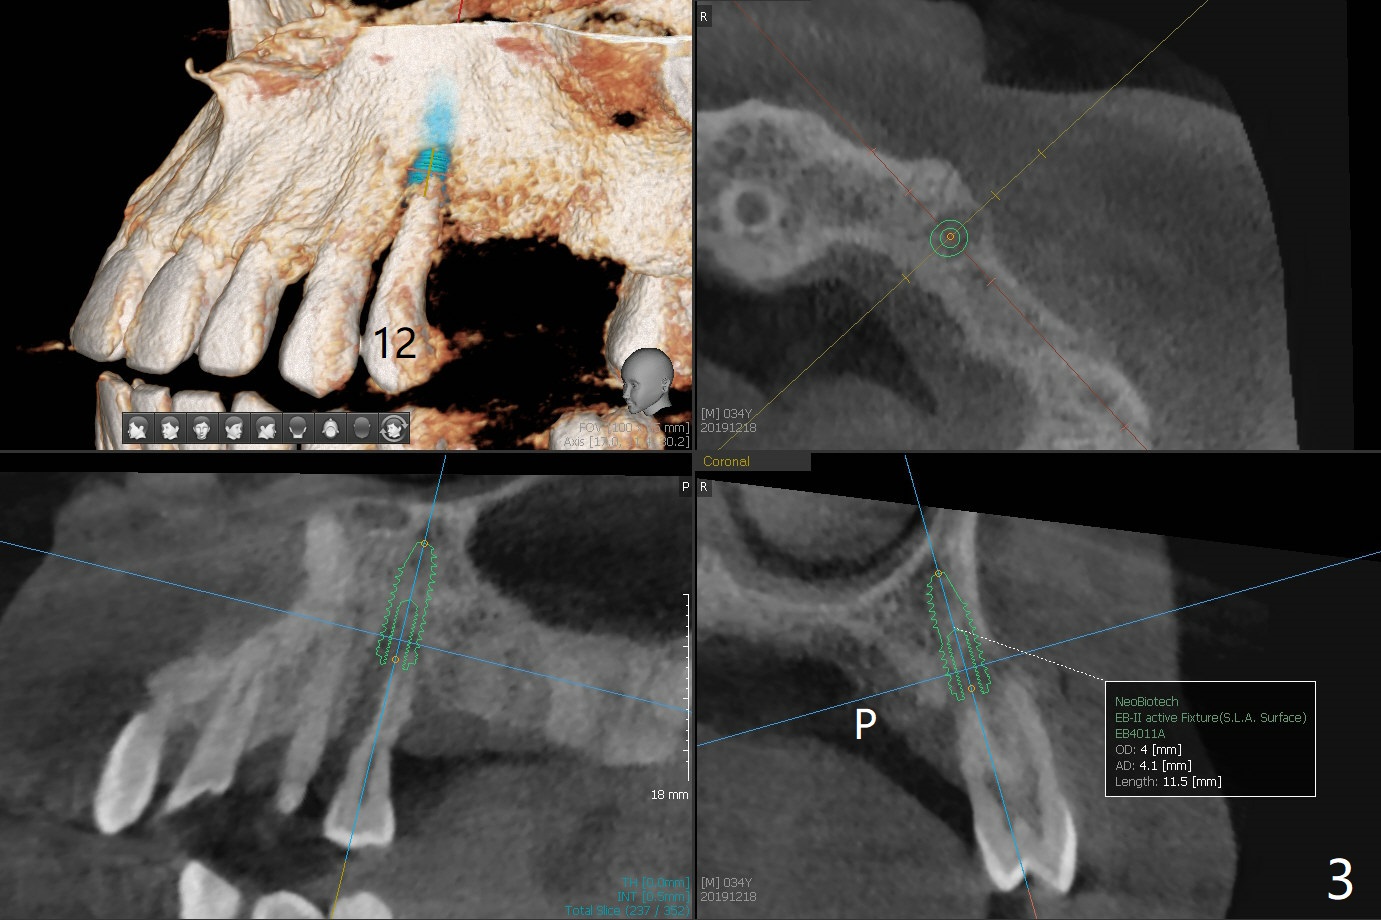

A 34-year-old man (smoker 1/2 ppd) presents to clinic for SRP and implant consultation (Fig.1). He wishes to restore UL first and the rest 2nd (Fig.2-5). Pay attention to placement level. OH will be emphasized, water pik and smoke cessation.